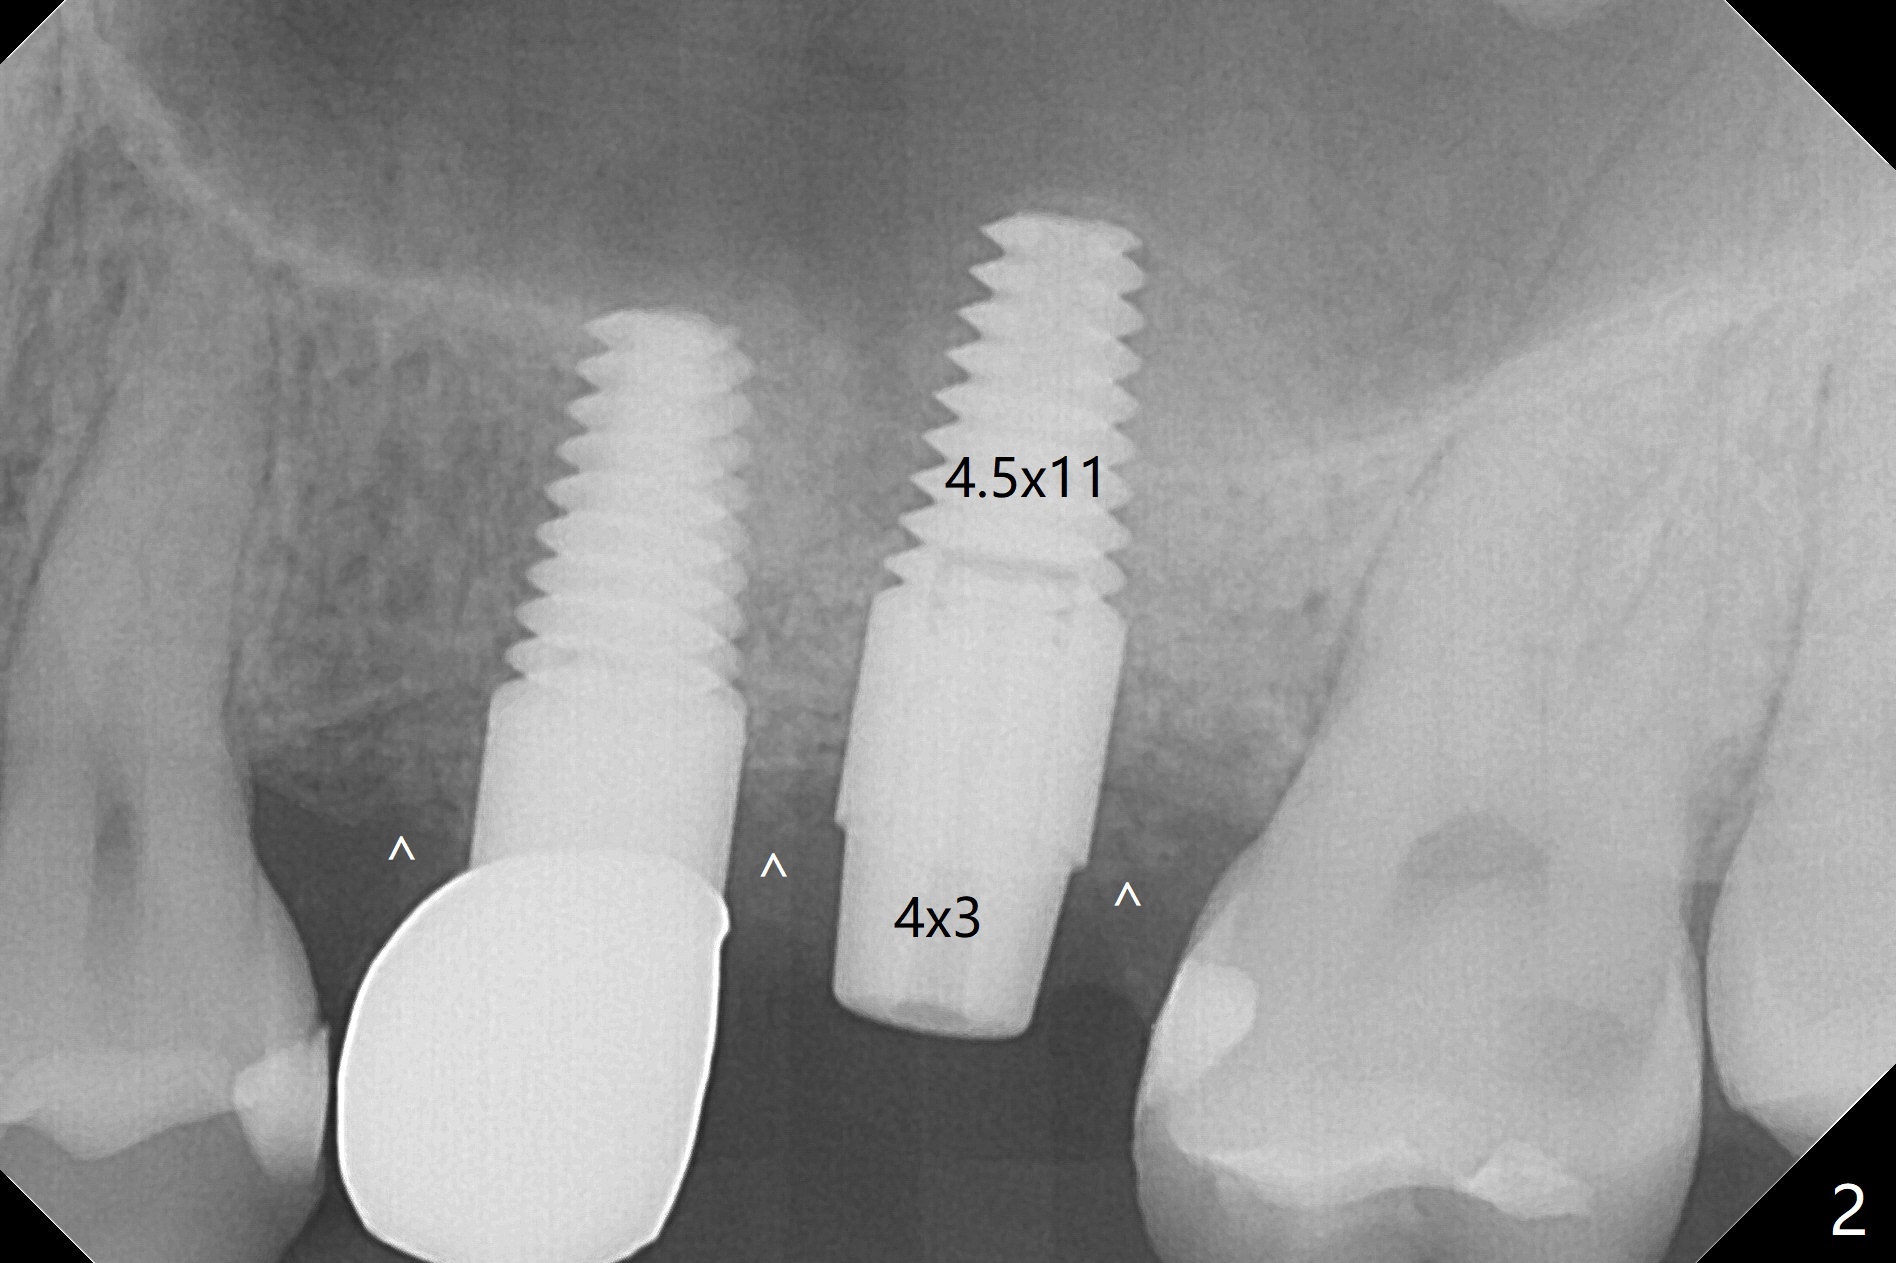

The ridge at #14 seems wide 6 months post implant removal and bone graft (before and after incision). In fact the palatal bone is low, which was the basis for periimplantitis. The new osteotomy is not initiated buccal enough. Immediate redo or guided surgery can avoid this complication. When a 4.5x14 mm tap is placed (Fig.1), the palatal threads are exposed. The buccal bone of the osteotomy has to be removed before placement of a 4.5x11 mm with 1 thread exposure palatal (Fig.2). Periimplantitis at #13 is found intraop (Fig.1 *). After removal of granulation tissue and use of Titanium brush, allograft is placed at #13 and 14 (Fig.2 ^) and is covered by PRF. Bone expansion is not conducted because of high bone density. If there is difficulty in restoration due to deep implant placement, it has to be backed up using torque wrench. The wound appears to heal by secondary intention 20 days postop (Fig.3). The implant is subgingival nearly 3 months postop (Fig.4 ^: gingival margin). It appears that the implant could be backed up (Fig.5,6). A 5 mm healing cuff is placed with Cetacaine and antibiotic ointment. The implant remains subgingival with the healing abutment 4 months postop. With Cetacaine and 2 gingival retraction cords, the implant margin is barely exposed. Large and deep gingivectomy is performed with Waterlase without too much pain. The gingival cuff is slightly erythematous and hemorrhagic on cementation (partially due to suboptimal oral hygiene, Fig.7). The margin is deep. Tatum implants are contraindicated when the gingiva is thick (Fig.8).